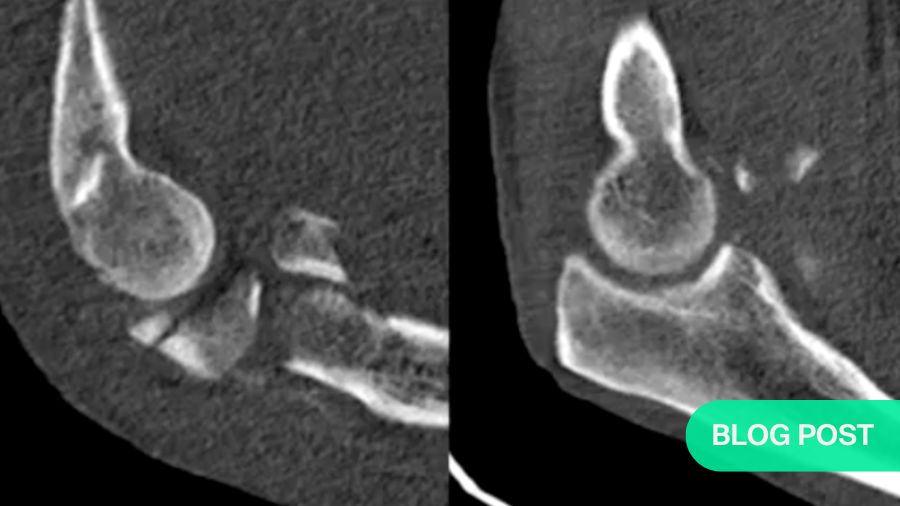

The coronoid fracture: classifying the damage

Shaun O’Driscoll’s coronoid classification system assesses the severity of coronoid fractures. The location and size of the fracture play a critical role in determining the treatment plan. For instance, a radial-sided tip fracture may not have as much impact on stability as a fracture involving the anteromedial facet.

The images demonstrate various coronoid fracture patterns, from minor tip fractures to complex fractures that involve multiple areas of the coronoid. Understanding the exact nature of these fractures—often via CT scans—is essential for effective treatment planning.